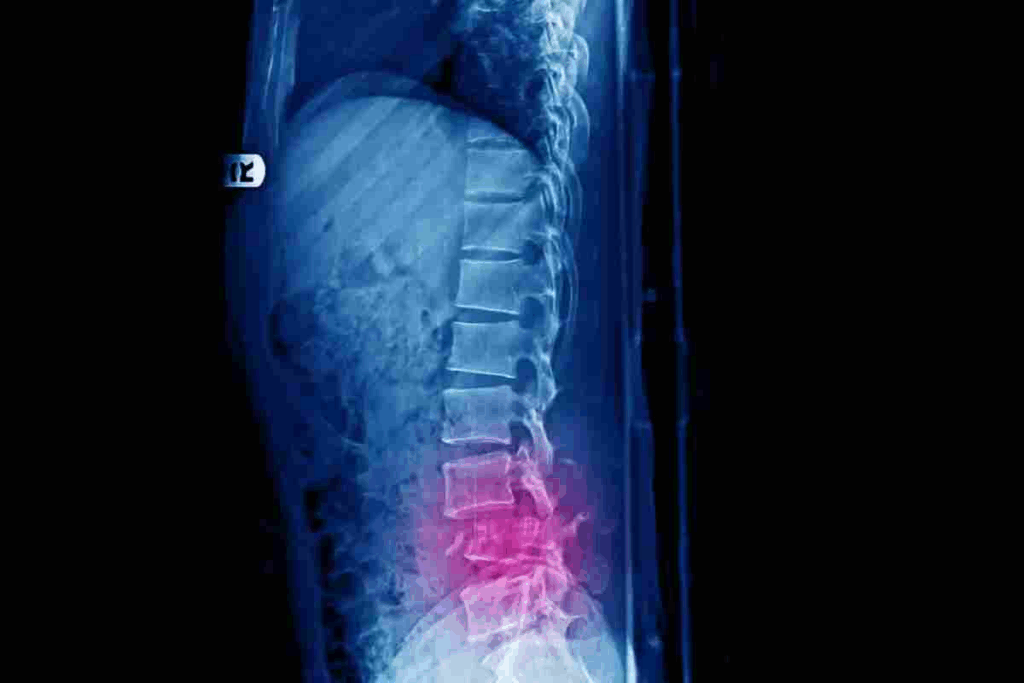

Discover how to heal a fractured vertebrae. Our guide covers proven steps for L1 compression and lumbar fracture treatment for a safe recovery.

A fractured vertebra can really change your life. It can mess with your posture, how you move, and how you feel overall. Seeing a spine expert early is key to getting better.

It’s important to know about vertebral fractures to get the right treatment. These fractures can really affect someone’s life if not treated well.

The lumbar spine and thoracic spine are where vertebral fractures often occur. The lumbar area, being a weight-bearing part, is more prone to fractures, like at L1 and L2. The thoracic spine can also get fractures, mainly at the thoracolumbar junction.